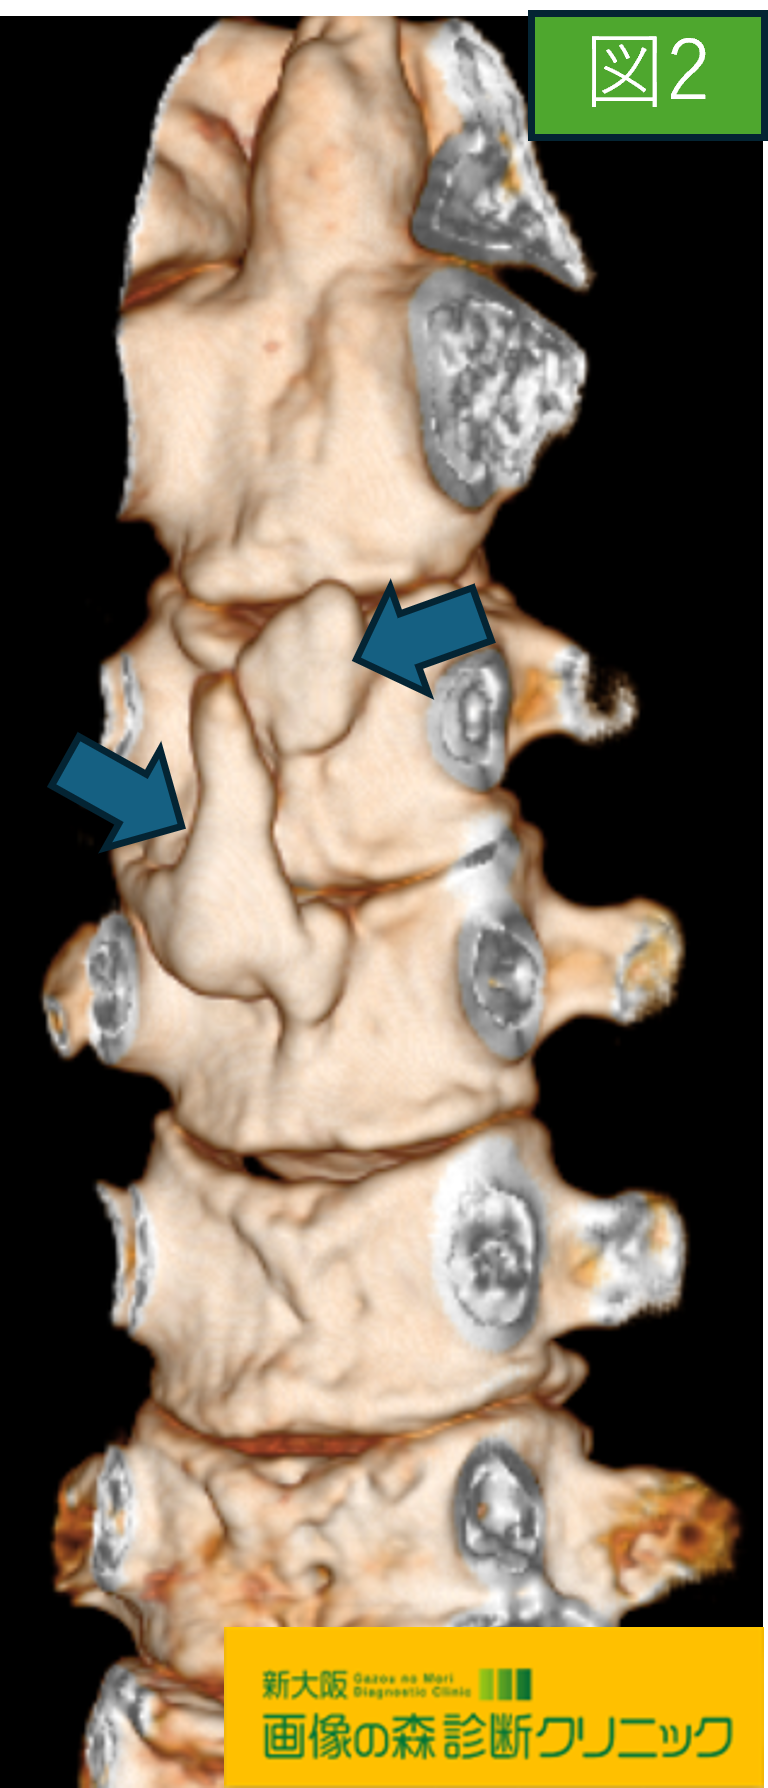

画像から図1・図2は頚椎CT画像です。

図1・図2はCTによる後縦靱帯骨化症を示しており、

脊柱管内の後縦靱帯を描出することができます。

またCTは骨化描出に優れており、図2の様に3Dでも後縦靱帯の骨化がはっきりと分かります。